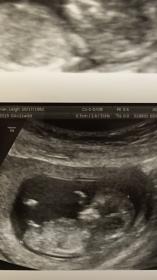

What are your thoughts on our 11 weeks/3 days ultrasound pic? I keep getting different predictions , so I thought I would bring it to the forum. Boy or Girl? I see boy using the nub theory, but maybe I am not looking at it the right way. Thank you!

Attachment 35607